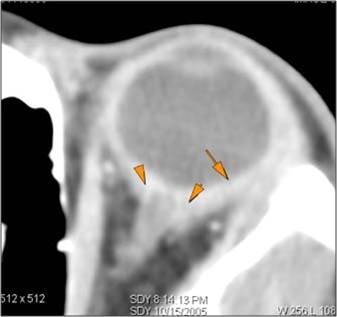

There is evidence of an infectious aneurysm.